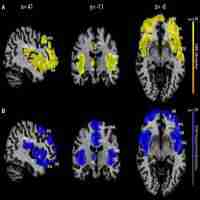

| Abstract | Background Facial emotion recognition (FER) is impaired in individuals with frontotemporal dementia (FTD) and Alzheimer’s disease (AD) when compared to healthy older adults. Since deficits in emotion recognition are closely related to caregiver burden or social interactions, researchers have fundamental interest in FER performance in patients with dementia. Purpose The purpose of this study was to identify the performance profiles of 6 facial emotions (i.e., fear, anger, disgust, sadness, surprise, and happiness) and neutral faces measured among Korean healthy control (HCs), and those with mild cognitive impairment (MCI), AD, and FTD. Additionally, the neuroanatomical correlates of facial emotions were investigated. Methods A total of 110 (33 HC, 32 MCI, 32 AD, 13 FTD) older adult participants were recruited from two different medical centers in metropolitan areas of South Korea. These individuals underwent an FER test that was used to assess the recognition of emotions or absence of emotion (neutral) in 35 facial stimuli. Repeated measures two-way analyses of variance were used to examine the distinct profiles of emotional recognition among the four groups. We also performed brain imaging and voxel-based morphometry (VBM) on the participants to examine the associations between FER scores and gray matter volume. Results The mean score of negative emotion recognition (i.e., fear, anger, disgust, and sadness) clearly discriminated FTD participants from individuals with MCI and AD and HC (F(3, 106) = 10.829, p < .001, = .235), whereas the mean score of positive emotion recognition (i.e., surprise and happiness) did not. A VBM analysis showed negative emotions were correlated with gray matter volume of anterior temporal regions, whereas positive emotions were related to gray matter volume of fronto-parietal regions. Conclusion Impairment of negative facial emotion recognition in patients with FTD is cross-cultural. The discrete neural correlates of FER indicate that emotional recognition processing is a multi-modal system in the brain. Focusing on the negative emotion recognition is a more effective way to discriminate healthy aging, MCI, and AD from FTD in older Korean adults. |